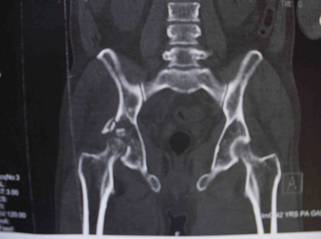

the hip. The reduction was checked with post reduction plain

radiograph and C\T scan. It was also checked the stability and

the range of motion of the hip. [fig.2] The right hip needed an

Fig.2: C/T scan after first try for reduction showing

that the left hip is reduced and a bony fragment in the right

acetabulum and a posterior wall fracture.